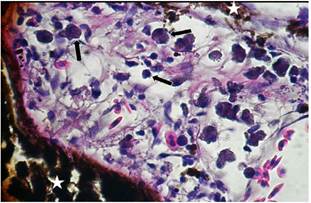

In 12.5% (2/16) of the cuts granulomas, composed by aggregated macrophages which were circumscribed by fibroblasts. Also, the hepatopancreas showed an inflammatory exudate (Figure 3-4) it was evidenced. Moreover, 75% (12/16) of sample fish showed necrosis. While in 56.25% (9/16) steatosis and hydropic degeneration of hepatocytes was evidenced.

Figure 4 Histopathological findings in Oreochromis niloticus. Photomicrograph of the hepatopancreas showing inflammatory exudate around of the hepatopancreas (star). Hematoxilin-Eosine, Scale bar = 20 µm.